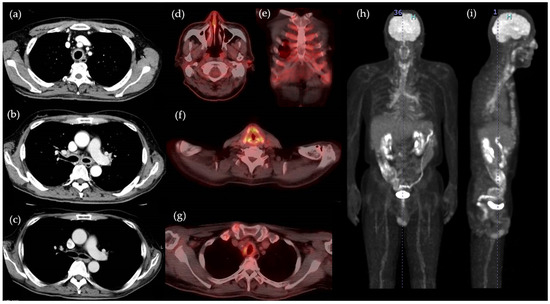

2. Case